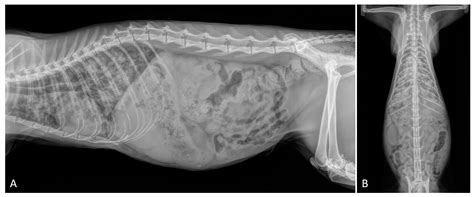

• Radiographs (X-rays): Chest X-rays can reveal inflammation, fluid, or other abnormalities in the lungs.